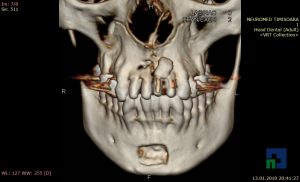

- Diagnosticul fracturilor:

- Unice

- Multiple

- Cu înfundare

- Complexe cranio-sinusale

- Complexe cranio-etmoidale

- Complexe cranio-orbitare

- Complexe cranio-faciale